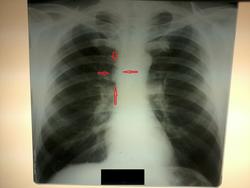

Мужчина, 50 лет. Дообследование после флюорографии. В проекции в/д правого легкого определяется гомогенное образование, с четким контуром, широким основанием прилегающее к тени средостения. На правом боковом снимке ОГК четко образование не определяется. Предполагаю наличие образования из средостения (если придерживаться правилам Ленка и Зенихиной). Хотелось бы узнать ваши мнения по данным снимкам. Заранее извиняюсь за качество, фотографии были сделаны на сотовый телефон.

Если имеется в виду доп. тень, проекционно прилежащая к восходящей аорте, то согласен с Вами. Требуется томографическое дообследование.

Стрелочки поставил на снимке в прямой проекции, про боковую уточнил в описании.

Дуга аорты извита, так что есть вариант,что это она и есть...Сделайте еще заднюю проекцию ,может будет лучше видно.

А разве это не аорта?

Может, и аорта. Но если у доктора сомнения - дообследуй.

Мне в 6 сегменте справа не нравится кольцевидная тень ! В прямой - она мало заметна , малоинтенсивна , а в боковой- очень даже видна . А на счет тени у средостения - да , нужно "докрутить " ( или скопически , или заднюю + косую)

Думаю, кольцевидная тень - скиалогия. Тоже сначала глаз зацепился, но потом как-то "рассыпалась" на элементы легочного рисунка. Да и такого характера истинное затемнение было бы и на прямом. На скопии (если будет) сразу будет понятно.